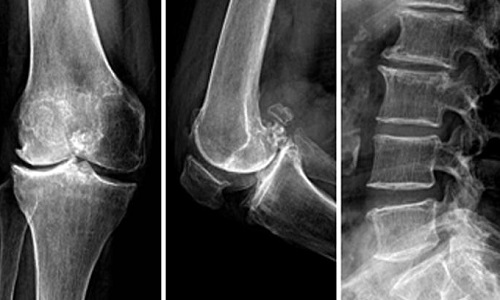

核心提示:骨质增生症多发于中年以上。一般认为由于中年以后体质虚弱及退行性变;长期站立或行走及长时间的持于某种姿势,由于肌肉的牵拉或撕脱、出血,血肿机化,形成刺状或唇样的骨质增生;跟着小编去认识一下关于骨质增生的相...

核心提示:骨关节炎是一种以关节软骨退行性变和继发骨质增生为特征的慢性关节疾病。此疾病有明显的年龄依赖性,60岁以上的人,约80%具有关节退变。  得了关节炎,还能打太极吗?  骨关节炎是一种以关节软骨退行性变和继发...